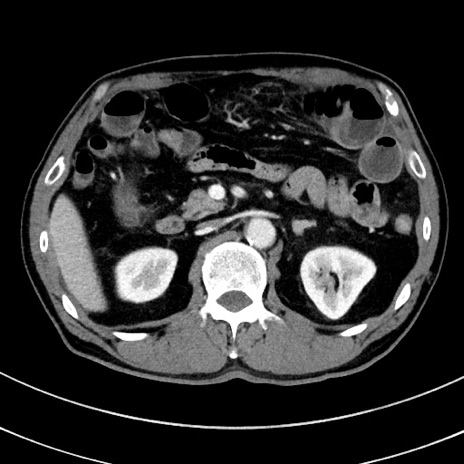

症例8(横断像)

【症例】 60歳代男性

【主訴】 黒色吐物

【現病歴】 4日前から嘔気自覚、2日前の朝食後にも嘔気あり、自分で手で嘔吐反射起こし嘔吐したところ血が混ざっていたため受診。

【既往歴】 5年前汎発性腹膜炎を伴う急性虫垂炎で手術、高血圧、前立腺肥大症、高脂血症

【身体所見】 腹部正中に手術癩痕あり 腹部平坦・軟圧痛なし膨満感あり

【データ】WBC 8400、CRP 4.54